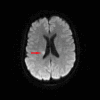

We present a case of a 52-year-old woman who had transient speech impediment and progressive numbness, weakness, and a purpuric rash affecting her limbs, with severe joint pains. Because she had a chest infection two weeks prior, her clinical presentation gave rise to a suspicion of post-infective vasculitis or post-infective polyneuritis. Further investigation proved this to be eosinophilic granulomatosis with polyangiitis (EGPA) presenting with purpura, mononeuritis multiplex, and cerebral infarction. Treatment with glucocorticoids and cyclophosphamide led to rapid remission. This case highlights the potential difficulty in diagnosing EGPA because of its multiple clinical manifestations and emphasizes the importance of a thorough review of the past medical history.